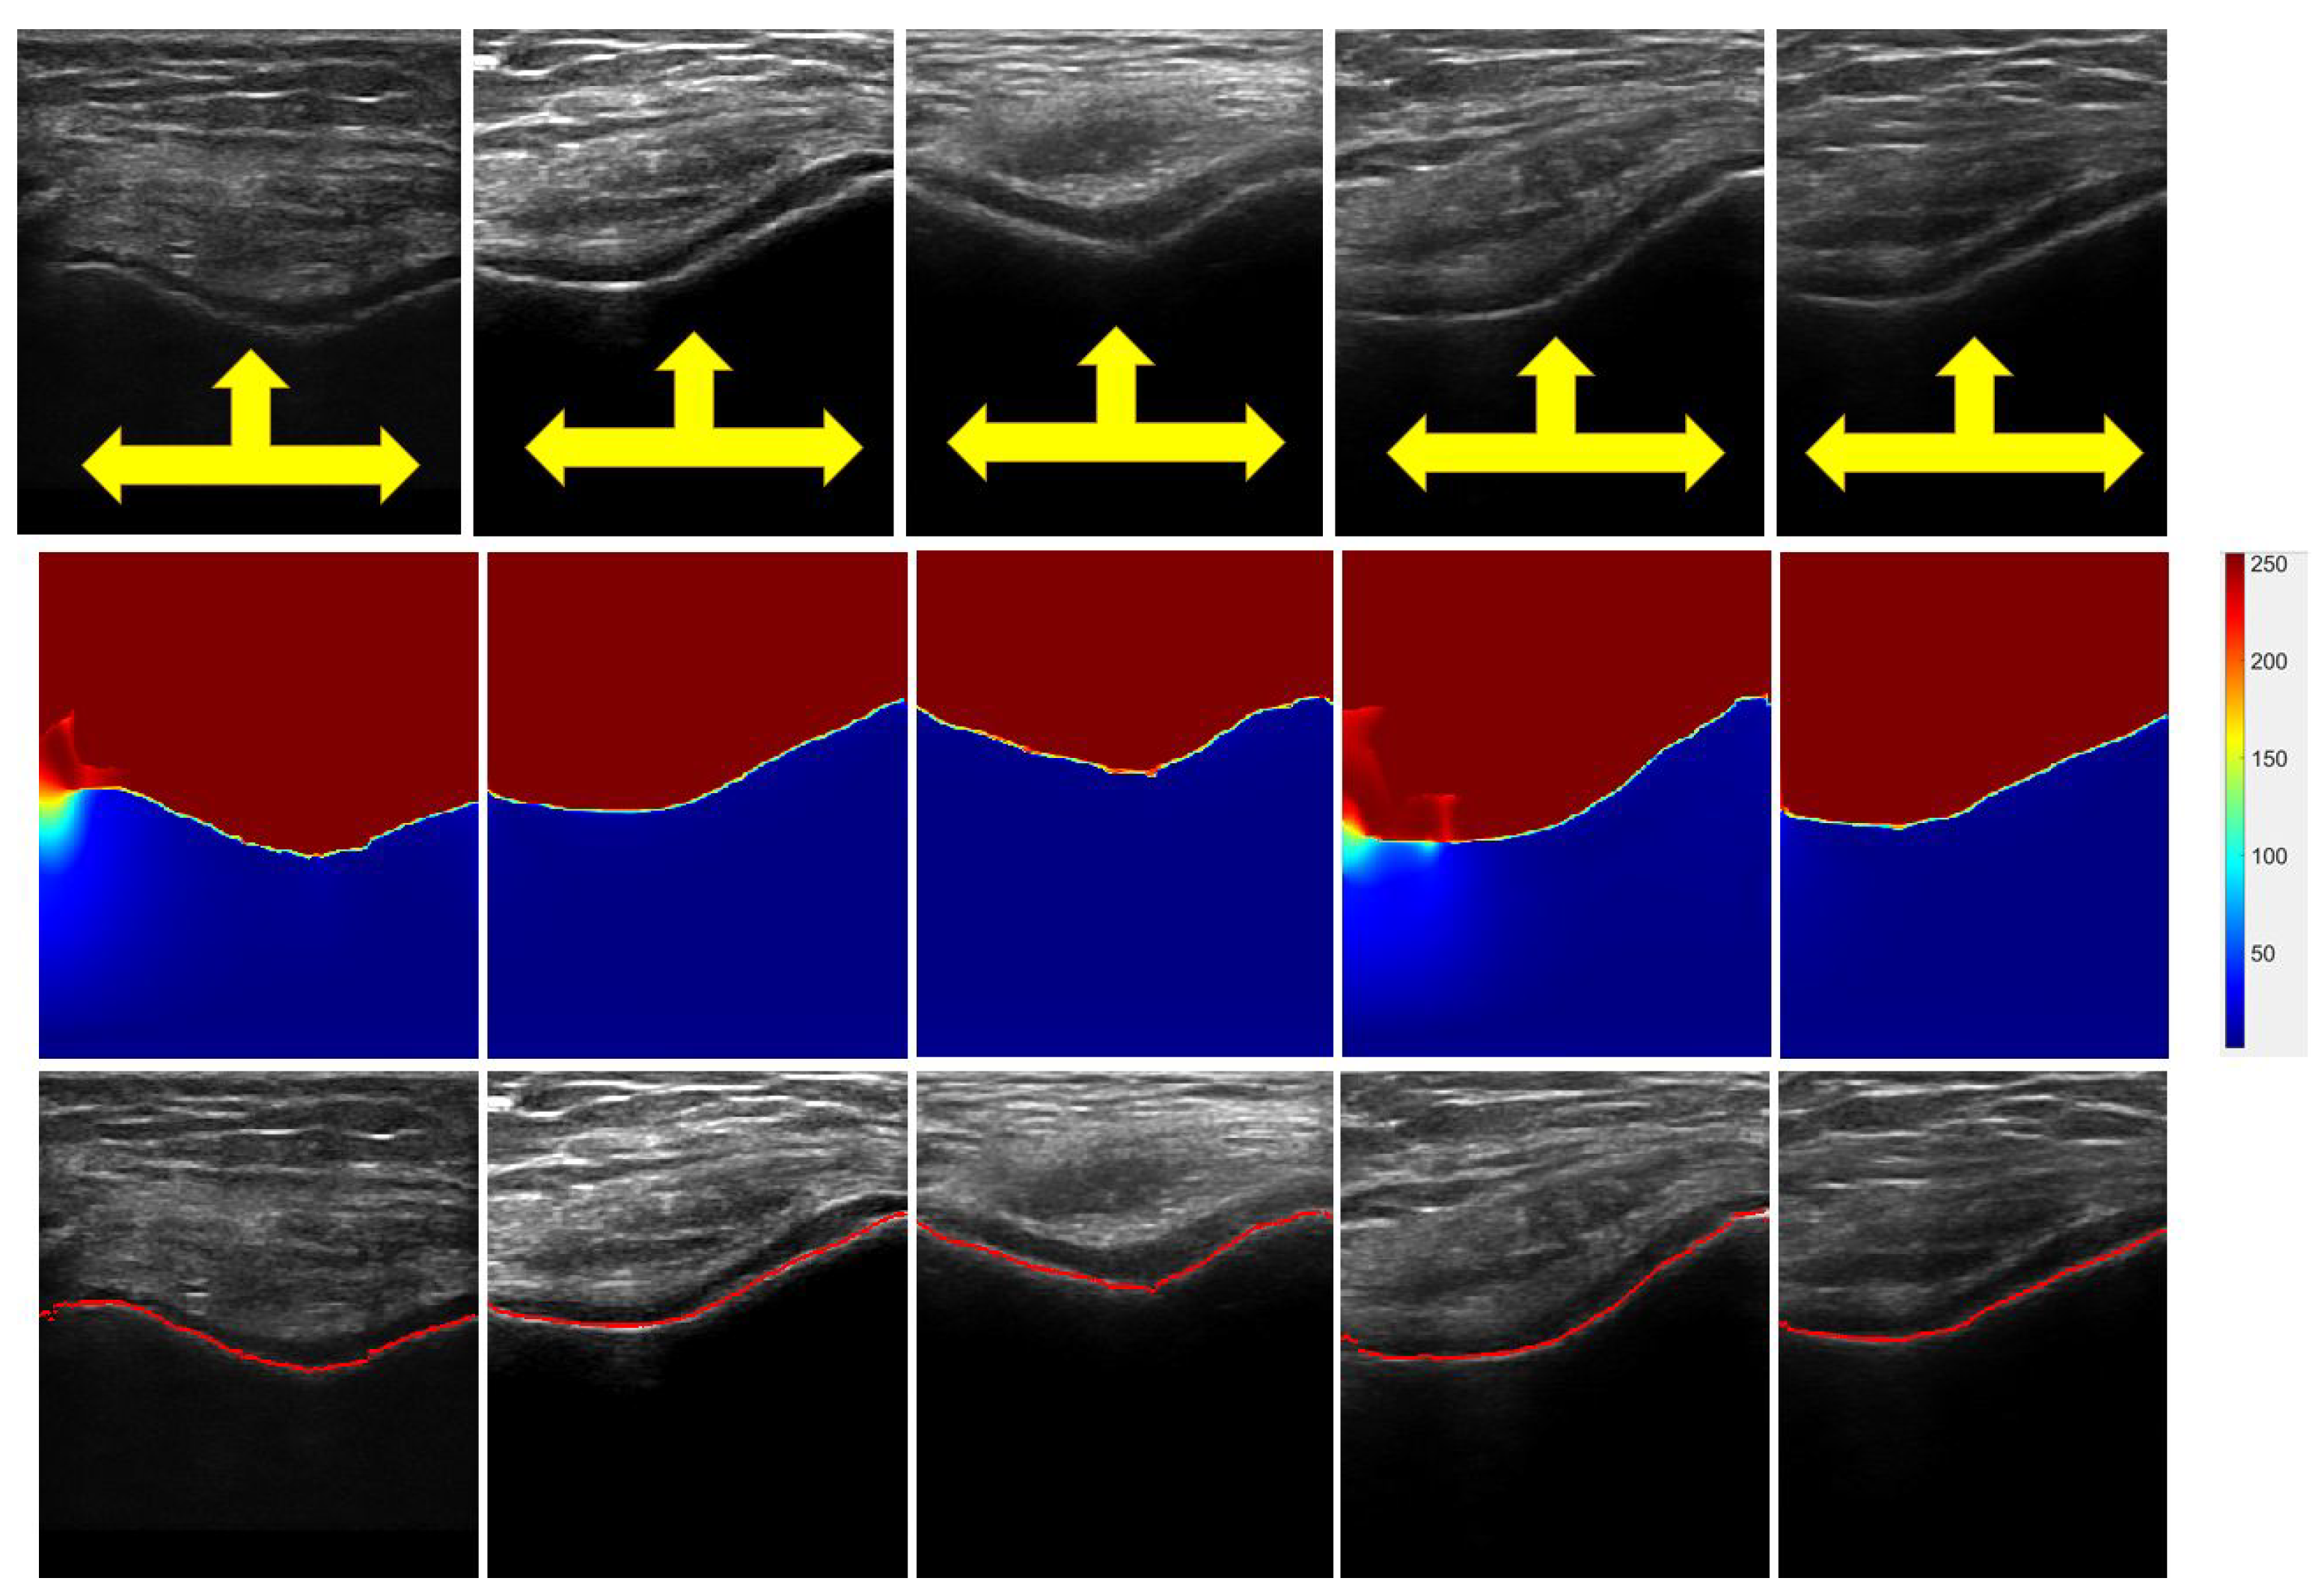

3.1. Cartilage-Segmentation Qualitative Results